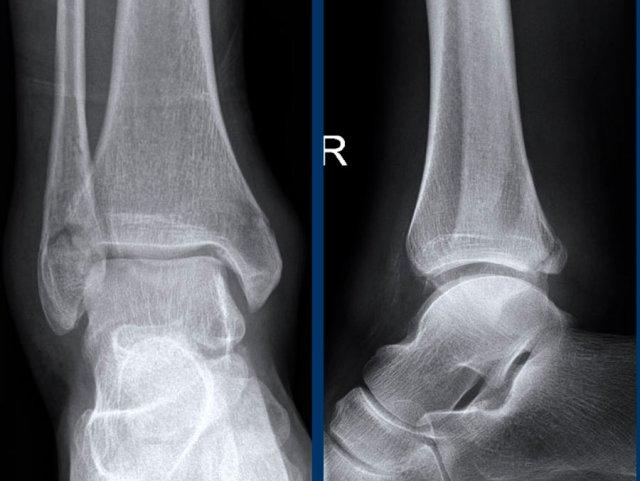

Ca 4 – Chấn thương cổ chân

Hình ảnh cho thấy những dấu hiệu gì?

Phân độ tổn thương trong trường hợp này là gì?

Nhấp vào hình ảnh để xem phóng to.